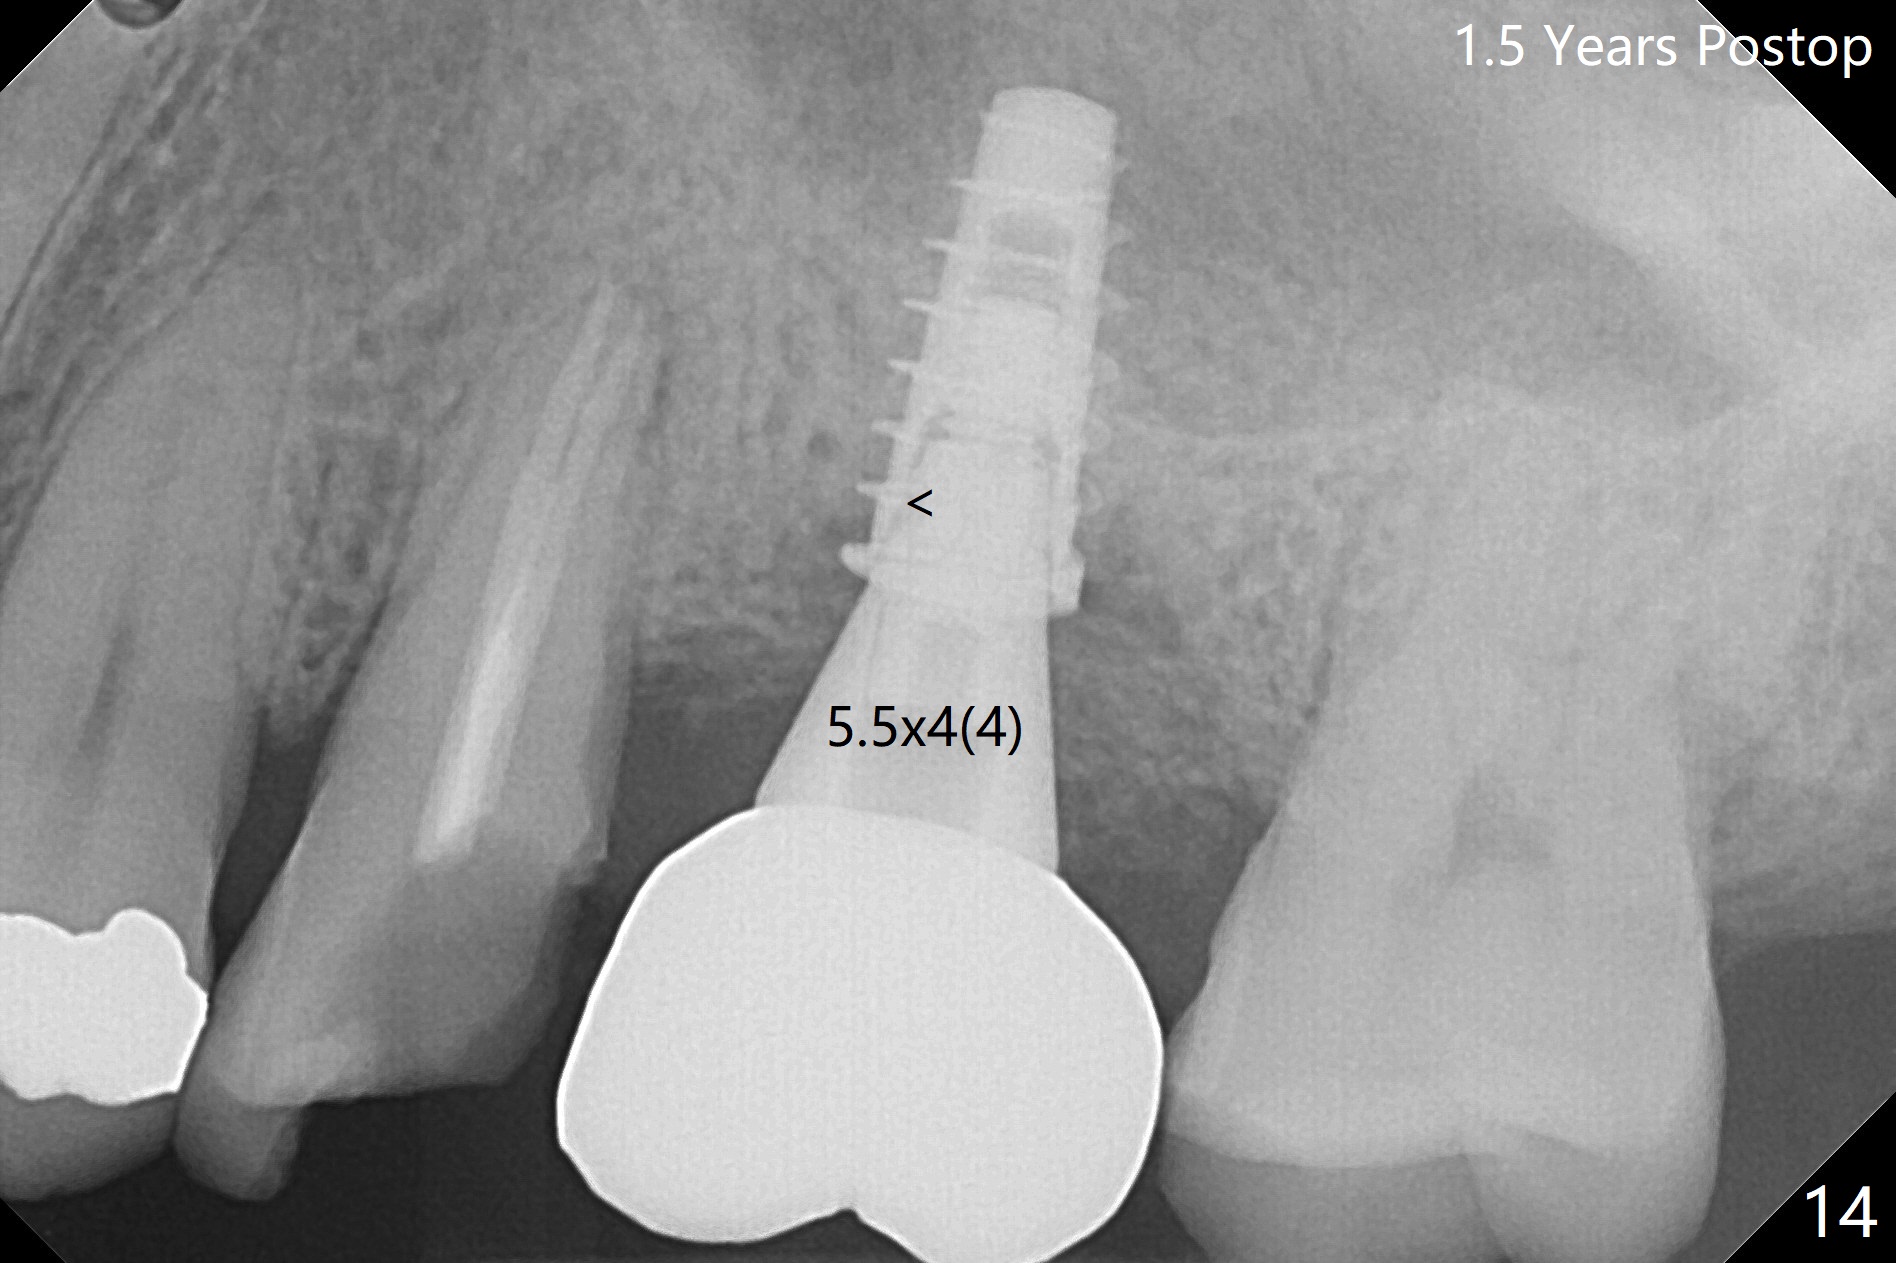

After extraction of the distobuccal residual root of the tooth #14 (Fig.1 arrow), the gingiva around the socket does not look like the keratinized one (Fig.2 *). An osteotomy through the distobuccal socket would seem too buccal for immediate implant. The palatal gingiva feels too tough to be stretched. An incision is made (Fig.3 dashed line); with elevation, the thick flap is transferred buccally (curved arrow). An osteotomy is initiated in the palatal bone with 1.5 mm drill, followed by Magic Expanders until 4.3 mm for 11 mm (Fig.4,5). Following Magic Drill 3.8x13 mm, the sinus membrane is found to be perforated. The latter is repaired with Osteogen plug. A 4.5x9 mm IBS implant is placed with 50 Ncm (Fig.6). Osteogen plug and allograft (Fig.7 *) are inserted into the remaining distobuccal socket (reduced after bone expansion). When a 5.5x4(4) mm abutment is placed, the transferred flap appears to be adapted to the distobuccal defect (Fig.8 *). Later one suture is placed for fixation. After provisional insertion, periodontal dressing is applied. Nine days postop, the periodontal dressing dislodges. When the loose provisional is removed for recementation, the flap seem to have healed (Fig.9 *). The gingiva heals around the abutment 5 months postop (Fig.9); the distal socket appears to heal while the bone graft remains at the crest (Fig.11,12). When #30 develops buccal abscess, the patient masticates on the left, leading to loss of composite at #13 (Fig.14); in fact the abutment at #14 is incompletely seated.